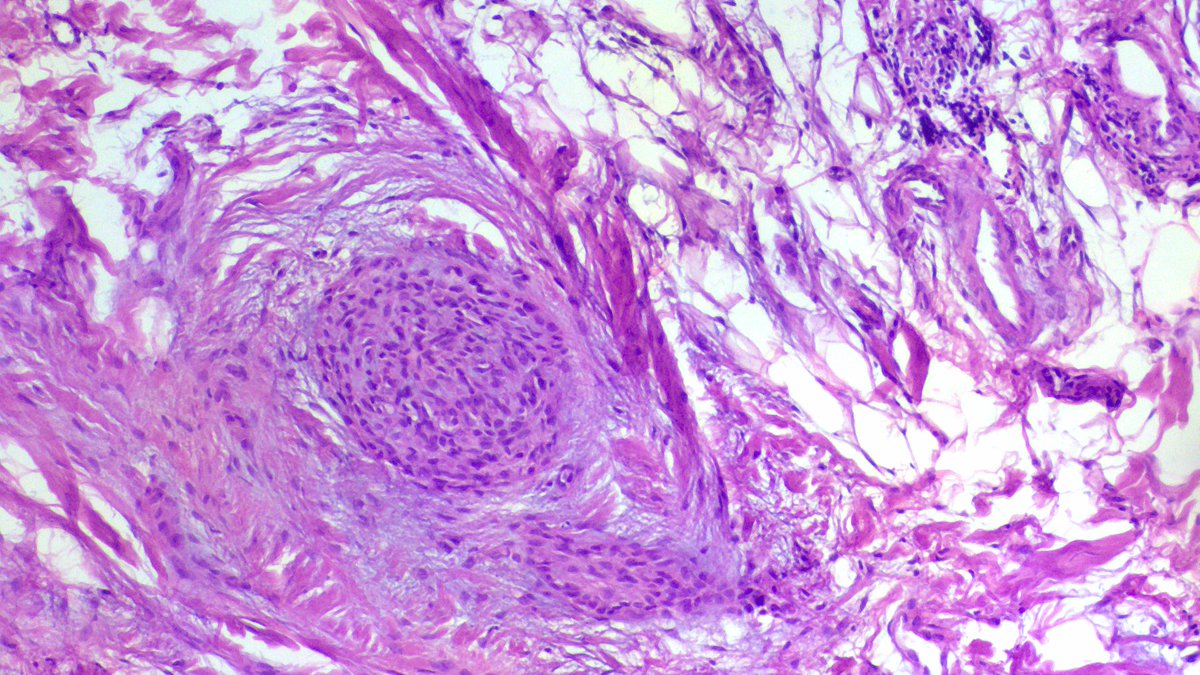

💎 Solitary Fibrous Tumor (SFT) involving the submandibular gland. 🔍 58-year-old male with a 5.5 cm left submandibular gland mass. ⚓️ Grossly, the lesion was a well-circumscribed, fleshy, firm white-tan mass with a solid whorled cut surface. 🔬 Microscopy showed a bland spindle cell neoplasm arranged in a “patternless pattern” with alternating hypo- and hypercellular areas, dense collagenized stroma, and prominent branching/staghorn-like vessels. Tumor cells showed minimal atypia and low mitotic activity. 🧪 IHC profile: • STAT6 nuclear positive •.CD34: diffuse positive • PanCK & S100: negative • SMA / Desmin: highlighted only vessel walls, negative in tumor cells • Beta-catenin: cytoplasmic granular staining without nuclear positivity 💡 Key points: • SFT is a rare mesenchymal neoplasm in salivary glands, most commonly affecting the submandibular gland and parotid. • The characteristic molecular alteration is the NAB2::STAT6 fusion, resulting from inversion at chromosome 12q13 and leading to nuclear STAT6 expression which is highly sensitive and specific for SFT. • Most SFTs behave indolently, but risk stratification depends on factors such as size, mitotic activity, necrosis, and patient age. Rare cases may recur or metastasize. 📚 Important morphologic clues favoring SFT: ✔ Patternless architecture ✔ Ropey collagen ✔ Staghorn vasculature ✔ Bland spindle cells ✔ Diffuse CD34 positivity & nuclear STAT6 positivity Case courtesy @annsmiley78 #PathTwitter #SurgPath #HeadNeckPath #SalivaryGlandPathology #SoftTissuePathology #SolitaryFibrousTumor #SubmandibularGland #Histopathology #Pathology #MedEd